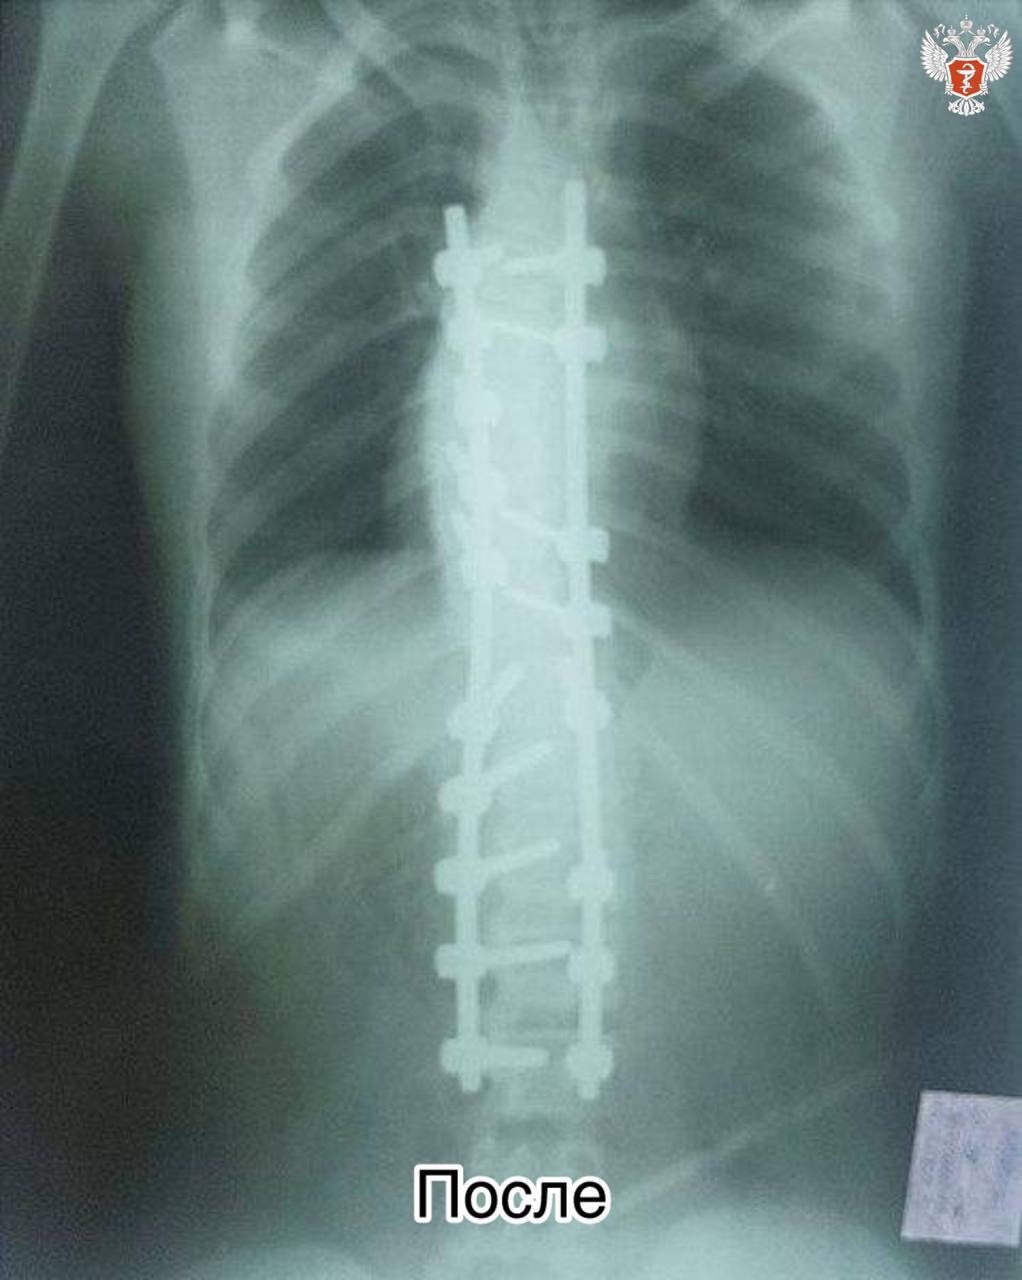

Позвоночник девочки по форме напоминал латинскую букву S. Из-за сильной деформации лёгкое оказалось сжато, а сердце сместилось в правую сторону.

— Мы поставили многоопорную винто-стержневую систему: в позвонки были введены транспедикулярные винты, по выпуклой и вогнутой стороне установлены отмоделированные титановые стержни, — рассказал оперирующий хирург Дмитрий Курдюмов.